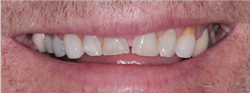

It has been estimated that about 90% of indirect restorations in the US are single crowns, and the majority of these single crowns are for posterior teeth. The phenomenal success of the original formulation of zirconia (3Y or Class 5 tetragonal zirconia) is now well proven. With the limitation of often less-than-desirable esthetic qualities, this material has become the most-used material for posterior crowns (figure 1).